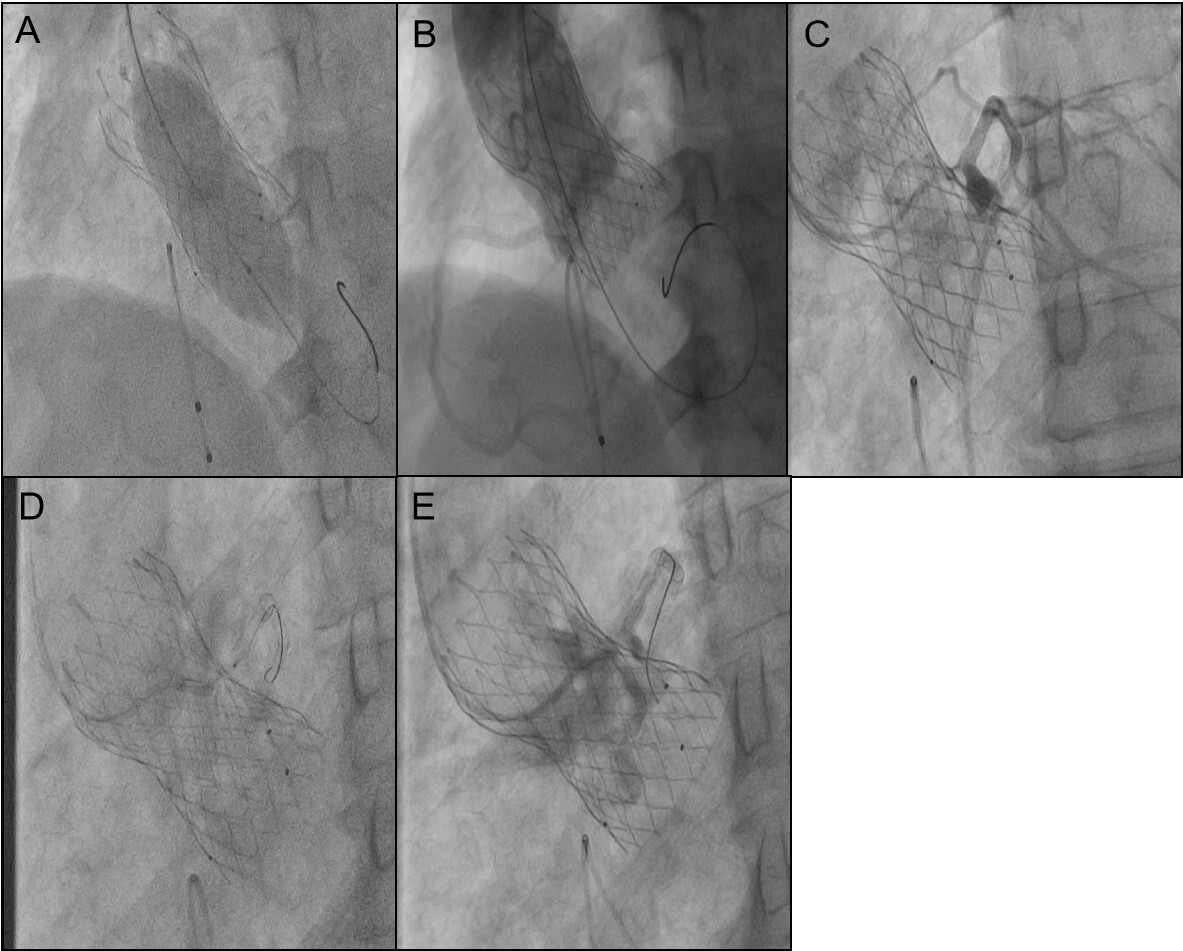

Implant a 3.5 mm×29 mm stent into the right coronary artery and a 3.5 mm × 24 mm stent into the left main trunk (Supplementary Figure S2). Post-coronary stent implantation, a 22 mm balloon was employed for aortic valve pre-dilatation. Imaging then demonstrated the relationship between the aortic root and the left coronary artery with the pigtail catheter in place (Figure 2A). A 32 mm VenusA Valve was subsequently implanted, and imaging indicated a gap between the native valve and the left coronary artery ostium at the aortic sinus base (Figure 2B). A 25 mm balloon was used for further dilation due to the inadequate expansion of the valve stent, and immediate imaging confirmed blood flow in the left coronary artery (Figures 3A,B). However, three minutes later, the patient exhibited significant chest discomfort and pain, with frequent premature ventricular contractions noted on cardiac monitoring. Rapid imaging detected an obstruction in the left coronary artery (Figure 3C). Efforts were made to navigate a 6F AL1 catheter through the prosthetic valve mesh to access the left coronary artery ostium, and a Pilot 50 wire was extended to the distal left anterior descending artery. Further dilation of the left coronary ostium and the obstructed native valve was performed using 2.0 mm, 2.5 mm, and 3.0 mm balloons (Figures 3D,E). IVUS assessment showed the coronary ostium no stenosis, indicating a marked improvement in coronary blood flow. The patient passed away suddenly one month after the procedure. For details, see Table 1.

Figure 3

(A) 25 mm balloon was used for further dilation due to the inadequate expansion of the valve stent. (B) Immediate imaging confirmed blood flow in the left coronary artery. (C) Obstruction in the left coronary artery tery. The gap between the leaflets and STJ is tiny. (D) Dilation of the left coronary ostium and the obstructed native valve was performed using 2.0 mm, 2.5 mm, and 3.0 mm balloons. (E) Angiography shows blood flow passing through.